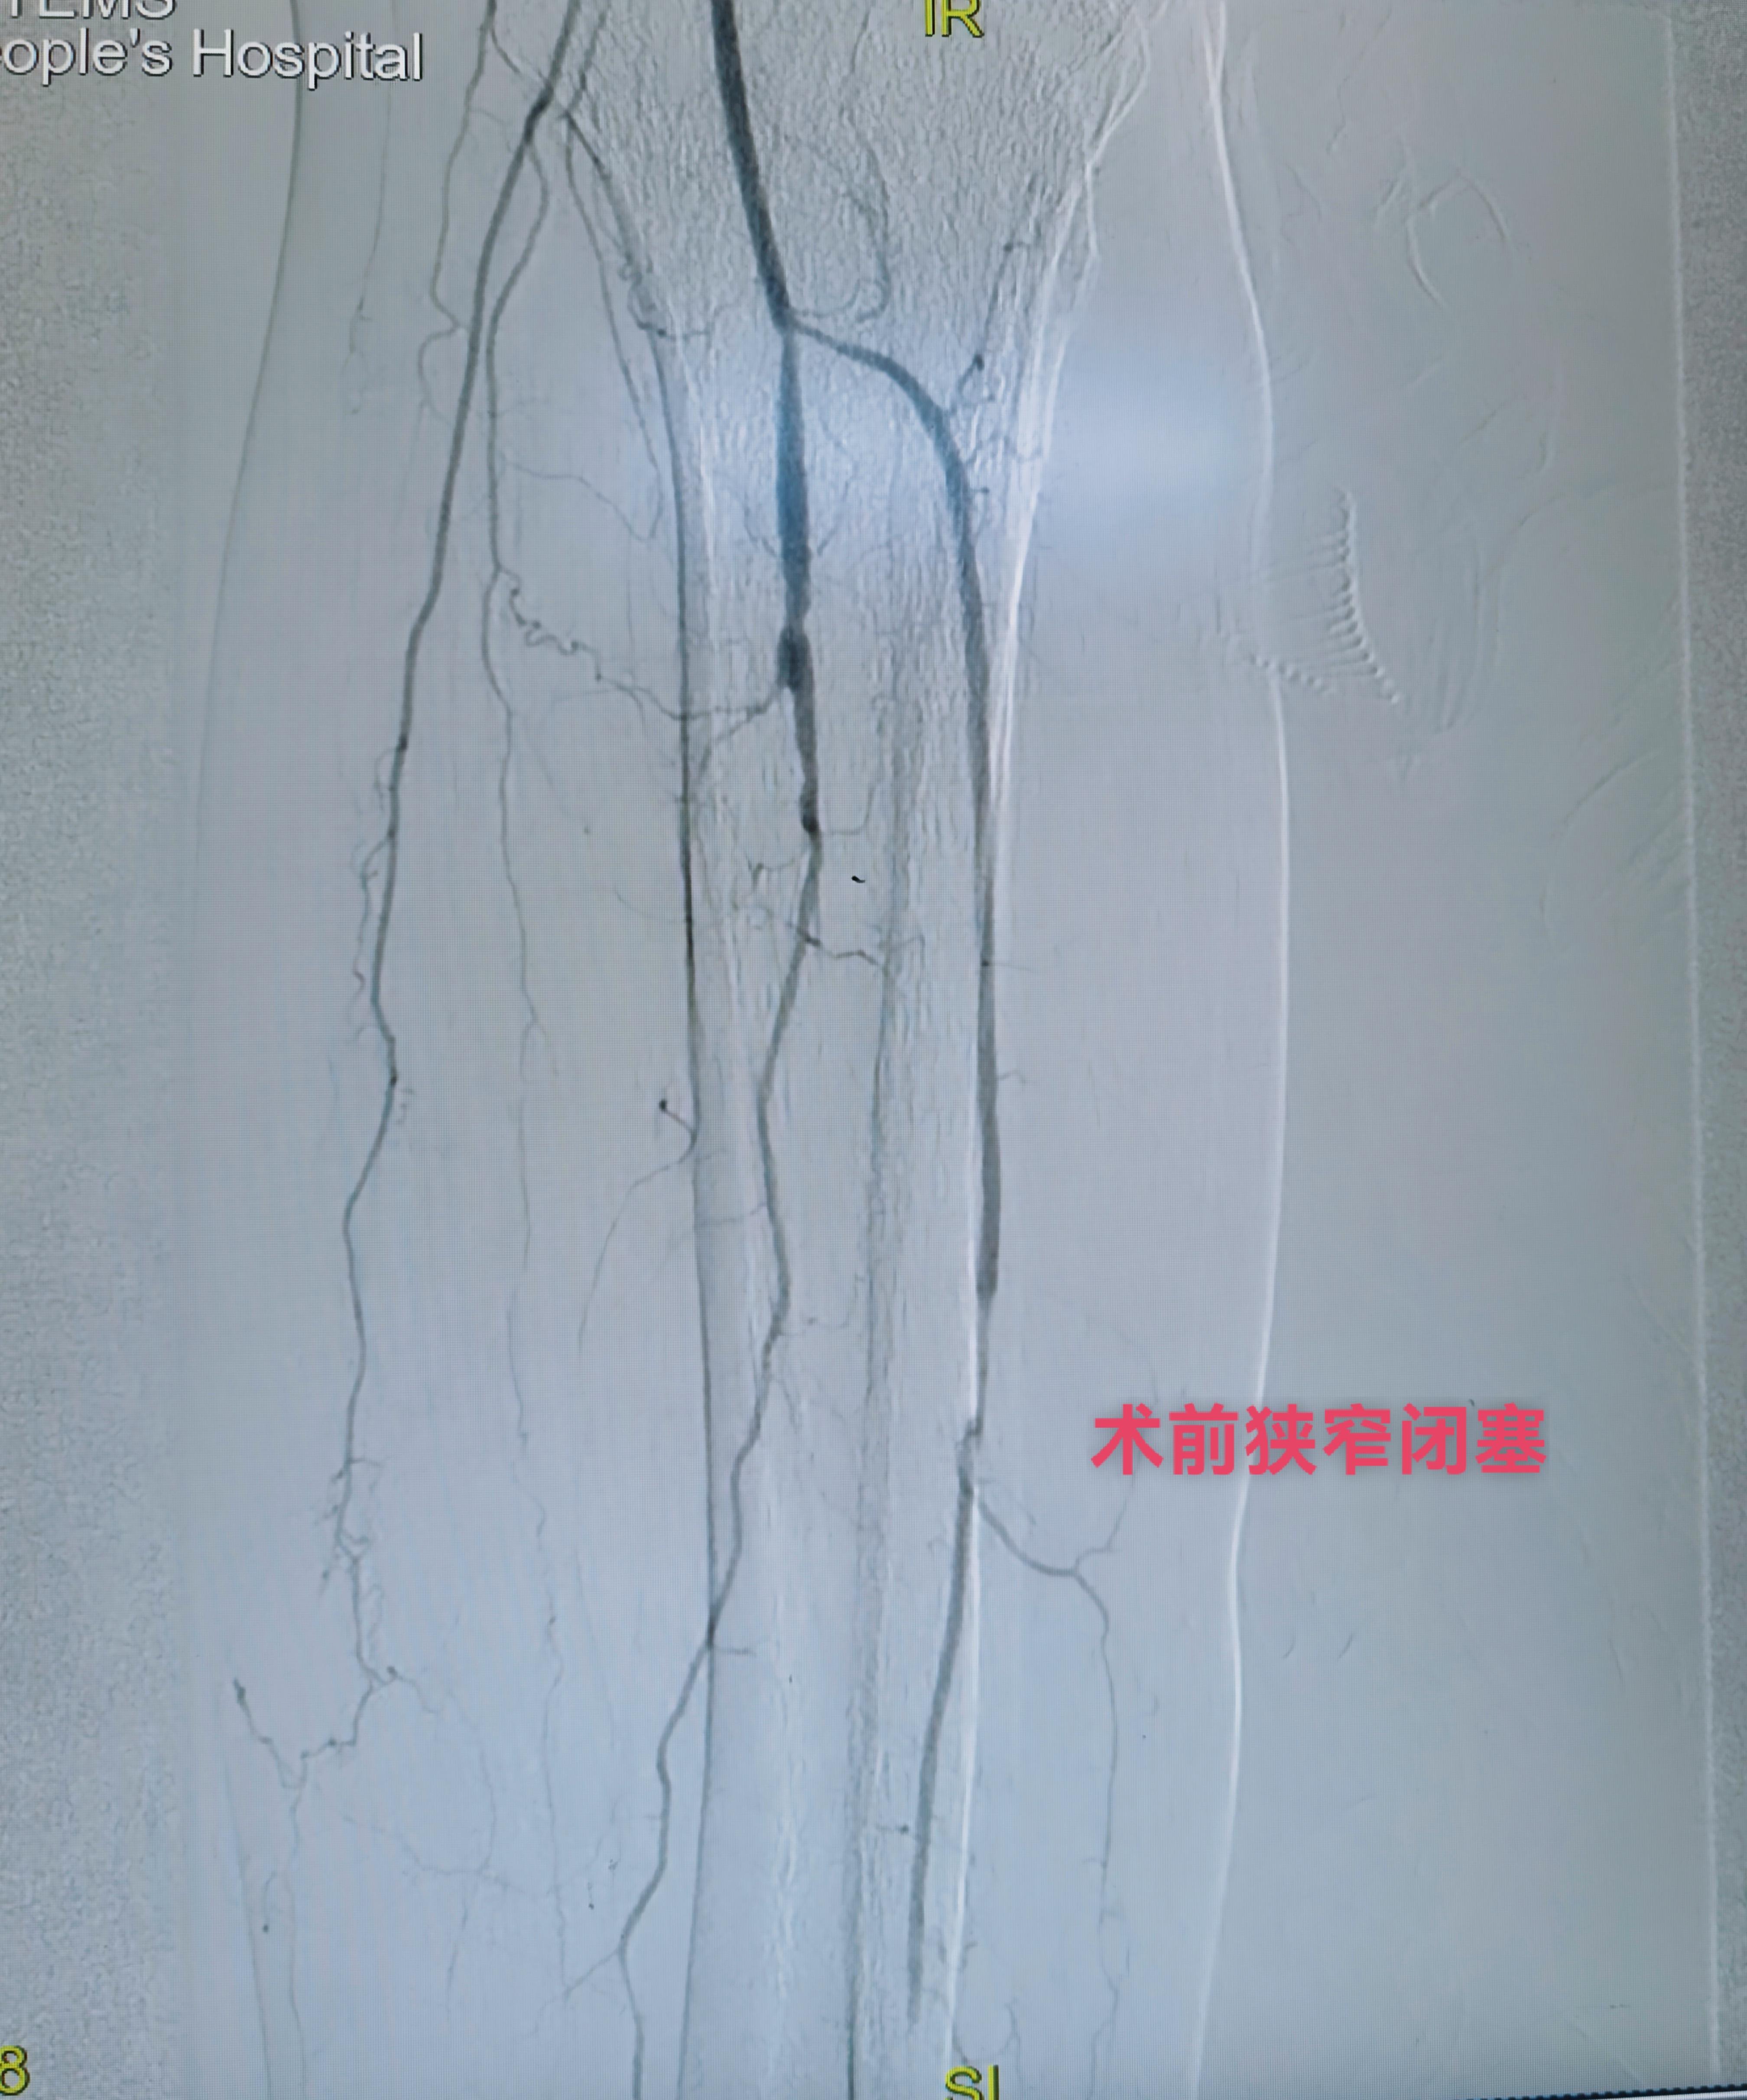

下午第一台糖尿病足三次腔内治疗再次未规律服药再次狭窄闭塞,下肢溃烂发黑,疼痛难忍。再次行球囊扩张术,术后皮温恢复,疼痛减轻。 第二台腮腺癌肝转移,经穿刺活检后证实后。行载药微球的灌注化疗栓塞。